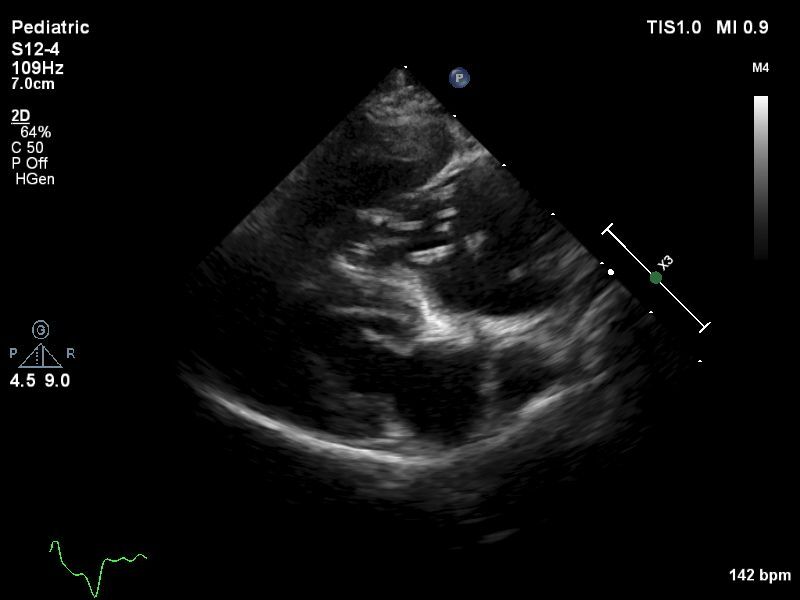

Die Diagnose wird meist nicht gestellt, weil ein Hund symptomatisch ist, sondern weil er aus einem endemischen Gebiet importiert wurde. Tatsächlich sind die meisten an uns überwiesenen Hunde asymptomatisch . Dann stellt sich die Frage, ob die Diagnose auch stimmt und ob entsprechend eine Behandlung indiziert ist. Gemäß der Empfehlung der American Heartworm Society (AHS) sollte die Diagnose basierend auf zwei positiven Testresultaten bestätigt sein. Das kann theoretisch ein Nachweis von Larven durch einen Knott’s Test plus ein positiver Antigentest sein. Nachdem ein Knott’s Test nicht als sensitiv gilt, führe ich diesen nie durch, sondern wiederhole bei einem überwiesenen Patienten zuerst einen Antigentest in einem anderen Labor. Teils können zwar Larven in einem Blutausstrich direkt unter dem Mikroskop gesehen werden; häufiger handelt es sich dabei aber um D. repens. Schließlich können in Einzelfällen adulte Würmer in der Lungenschlagader echographisch dargestellt werden, was dann als beweisend gilt.